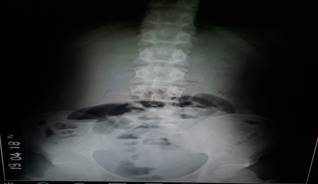

Radiografía de abdomen simple de pie y acostado: se observan asas intestinales distendidas y niveles hidroaéreos. Sugerente de oclusión intestinal (Figura 1).